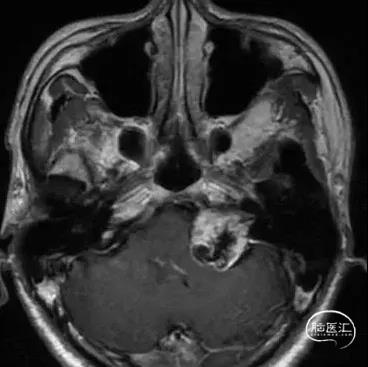

CASE 2 [ 左侧大型听神经瘤 ]

患者:男, 56y,左耳听力下降半年加重3月

肿瘤最大径约3.6cm

术前影像资料

扩大的内听道